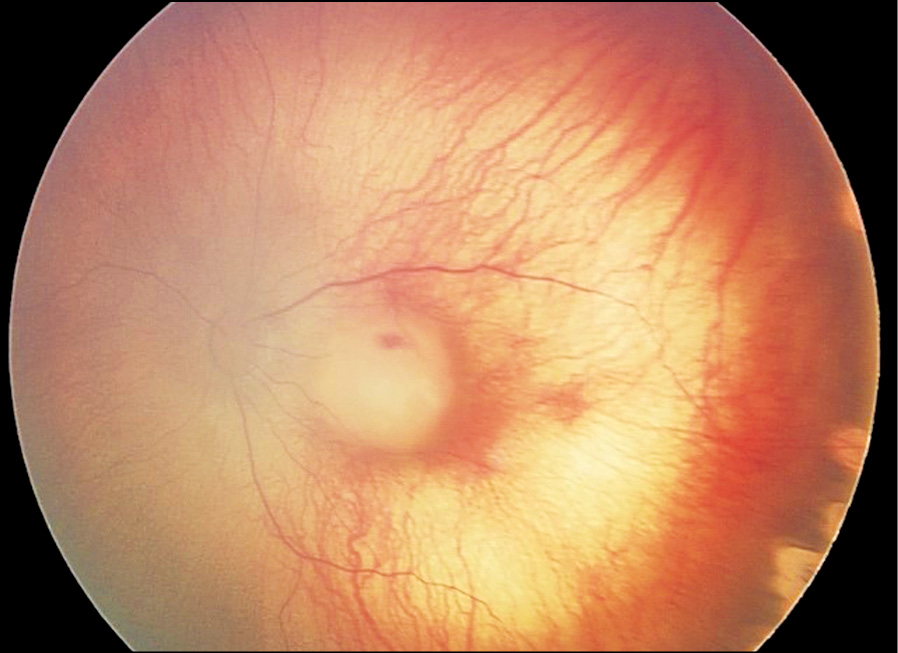

Клинический случай 1. Недоношенный мальчик, рождённый на 29-й недели гестации в результате экстракорпорального оплодотворения, из двойни, с массой тела 1350 г. Находился на лечении и выхаживании в СПб ГБУЗ «ДГБ №1» (в 2019 г. переименована в СПБ ГБУЗ «Детский городской многопрофильный клинический специализированный центр высоких медицинских технологий»). Первичный офтальмологический скрининг с помощью педиатрической ретинальной камеры «RetCam3» (США) проведён при достижении ребёнком 31-й недели постконцептуального возраста (ПКВ). При этом выявлены признаки незавершённости васкуляризации сетчатки на крайней периферии обоих глаз. В процессе регулярного мониторинга за состоянием глазного дна была диагностирована активная РН 2-й стадии с локализацией в зоне II сетчатки (рис. 1). К 36-й неделе ПКВ прогрессирование заболевания достигло порога (стадия 3, «плюс-болезнь»), что потребовало лазерного хирургического лечения. Для проведения лазерной коагуляции аваскулярных зон сетчатки использовали диодный лазер с длиной волны 532 нм (Iridex, США) и транспупиллярный доступ. После выписки из стационара было продолжено динамическое наблюдение офтальмологом в кабинете катамнеза амбулаторно-поликлинического отделения данного учреждения, где у пациента в 38 недель постконцептуального возраста зарегистрирован и документирован индуцированный регресс РН (рис. 2). Следующий осмотр состоялся через 2 недели (ПКВ — 40 недель), во время которого был обнаружен очаг опухоли в макулярной области сетчатки (рис. 3). Так как результаты всех обследований глазного дна с помощью RetCam регистрировались и архивировались в базе данных пациента, ретроспективный анализ ранее выполненного изображения показал наличие точечного очага опухоли, расположенного в центре макулы левого глаза (рис. 2), который корректно не интерпретировали, сосредоточив внимание на клинической картине РН. Несмотря на сверхмалый размер очага данный случай РБ относится к группе В исходя из его локализации.

Рис. 2. Индуцированный (после лазерной коагуляции сетчатки) регресс РН.

Fig. 2. Induced (after laser coagulation of the retina) regression ROP.

Рис. 3. Очаг ретинобластомы в макулярной зоне сетчатки.

Fig. 3. Retinoblastoma focus in the macular zone of the retina.

Отсутствие отягощённого семейного анамнеза и настороженности относительно РБ в данной ситуации не позволило диагностировать новообразование на 38-й неделе ПКВ. Однако данный клинический пример демонстрирует высокую разрешающую способность педиатрической ретинальной камеры, а также позволяет проследить быстрый рост злокачественного новообразования у недоношенного младенца в первые месяцы жизни.